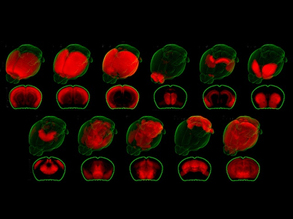

Developing Zone